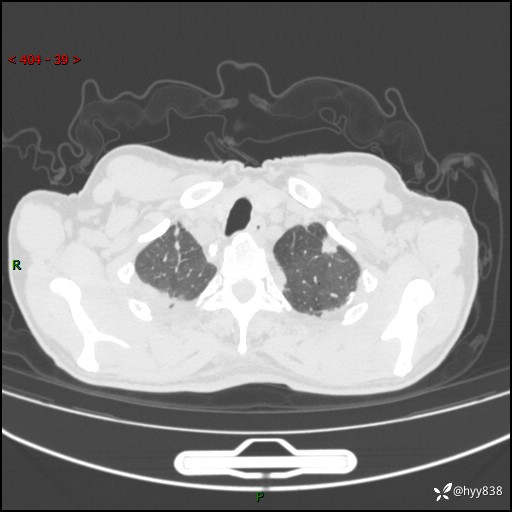

辅助检查:CT

胸部CT平扫